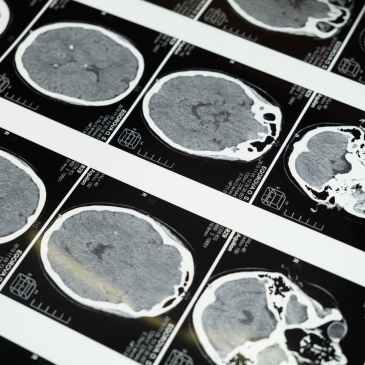

La hidrocefalia: una vida sin cerebro